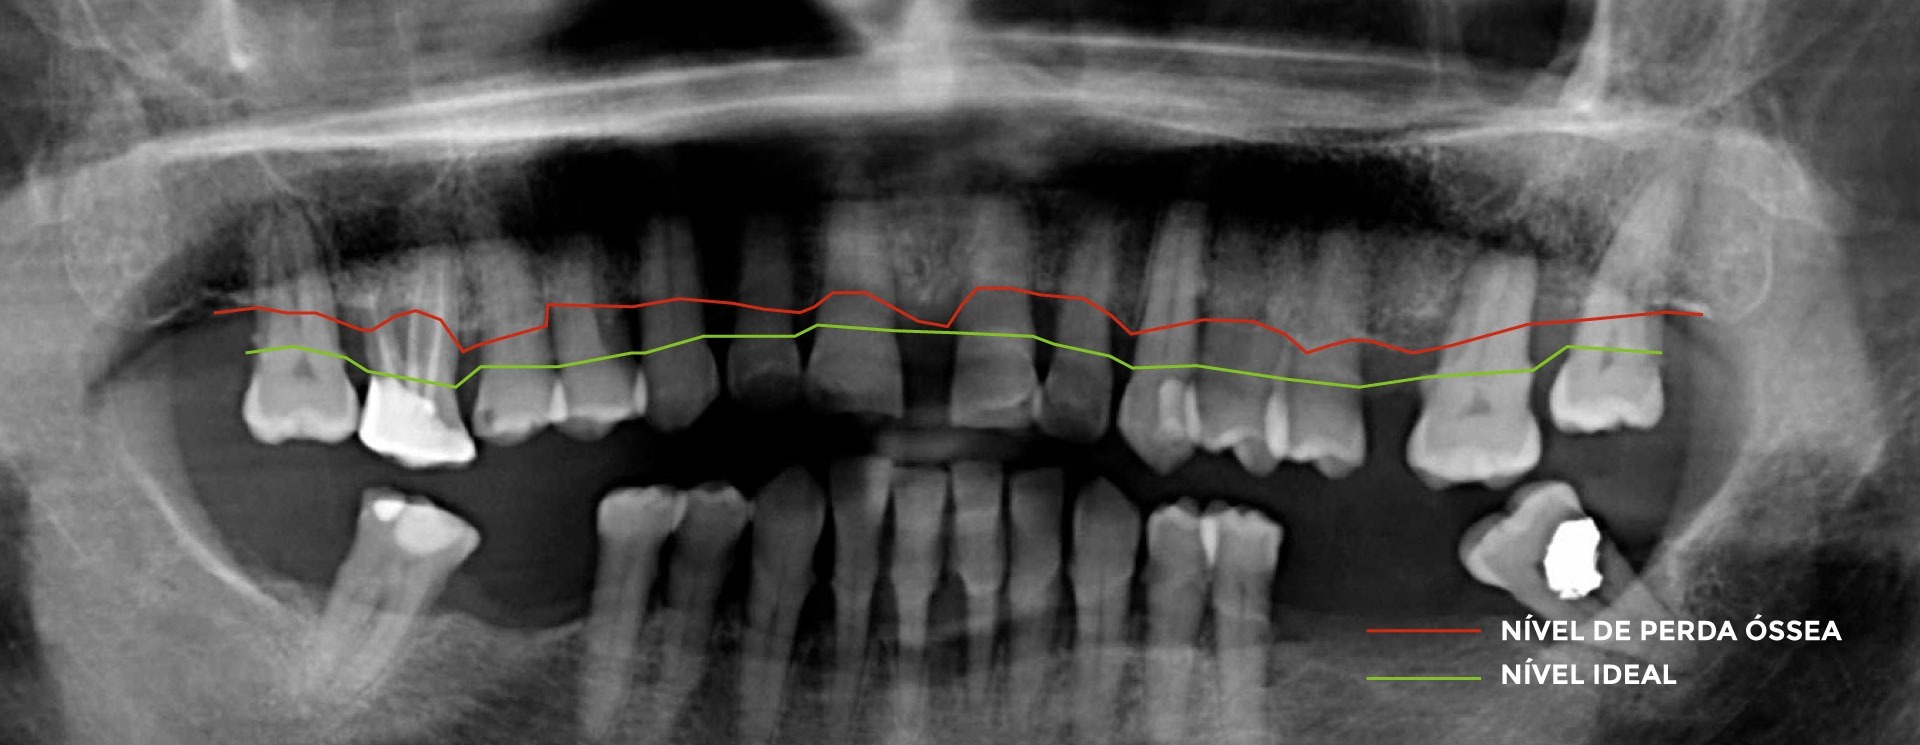

Periodontite

Progressão inflamatória da doença periodontal que leva à destruição dos restantes tecidos de suporte dos dentes: o ligamento periodontal (conjunto de fibras que existem entre os dentes e o osso maxilar) e o osso que suporta os dentes.

Para avaliação de suporte ósseo em redor dos dentes , o exame radiográfico é fundamental.